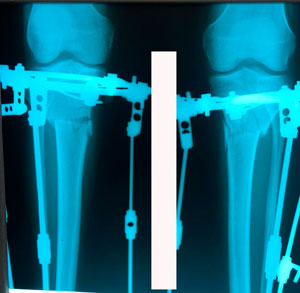

на фиксации

Дата операции - 29.01.2020

Дата снятия аппаратов - 19.05.2020